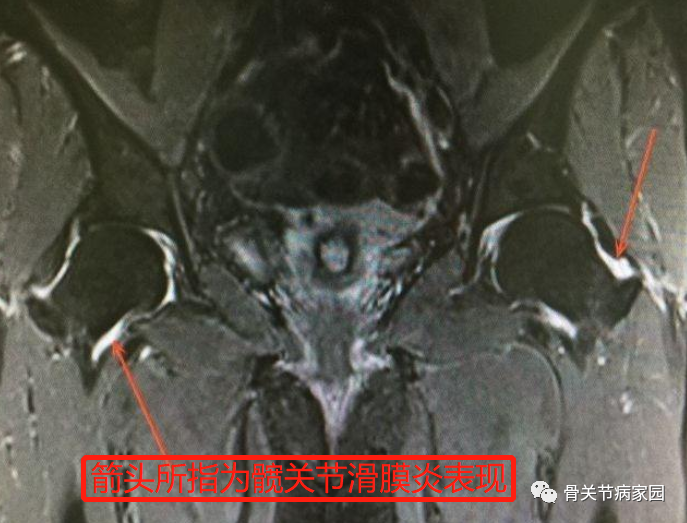

最后,辅助检查有助于疾病的诊断。髋关节X线片能明显看出关节囊范围,若关节积液明显则可以表现为关节囊膨胀,严重者股骨头可向外侧移位,呈半脱位征象;髋关节MRI能够直接反映关节积液情况,同时能够判断积液量,对于诊断滑膜炎及原发病有着特殊的意义,实验室检查缺乏特异性指标,白细胞及中性粒细胞不高或轻度升高,其他项目如结核菌素试验类风湿因子、抗核抗体、C-反应蛋白等检查能够确诊一些原发髋关节疾病,如髋关节结核、类风湿性关节炎等;此外,关节腔积液的穿刺检查有助于明确积液的理化性质,对于对于疾病鉴别诊断及治疗均有指导意义。